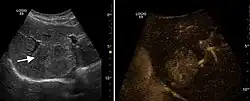

The ultrasound appearance is a well defined lesion, with very thin, almost unapparent walls, without circulatory signal at Doppler or CEUS investigation. The content is transonic suggesting fluid composition. The presence of membranes, abundant sediment or cysts inside is suggestive for parasitic, hydatid nature. Posterior from the lesion the acoustic enhancement phenomenon is seen, which strengthens the suspicion of fluid mass. They typically displace normal liver vessels but no vascular or biliary invasion occurs.

Hydatid liver cyst. Diagnostic criteria are the presence of membranes and sediment inside.